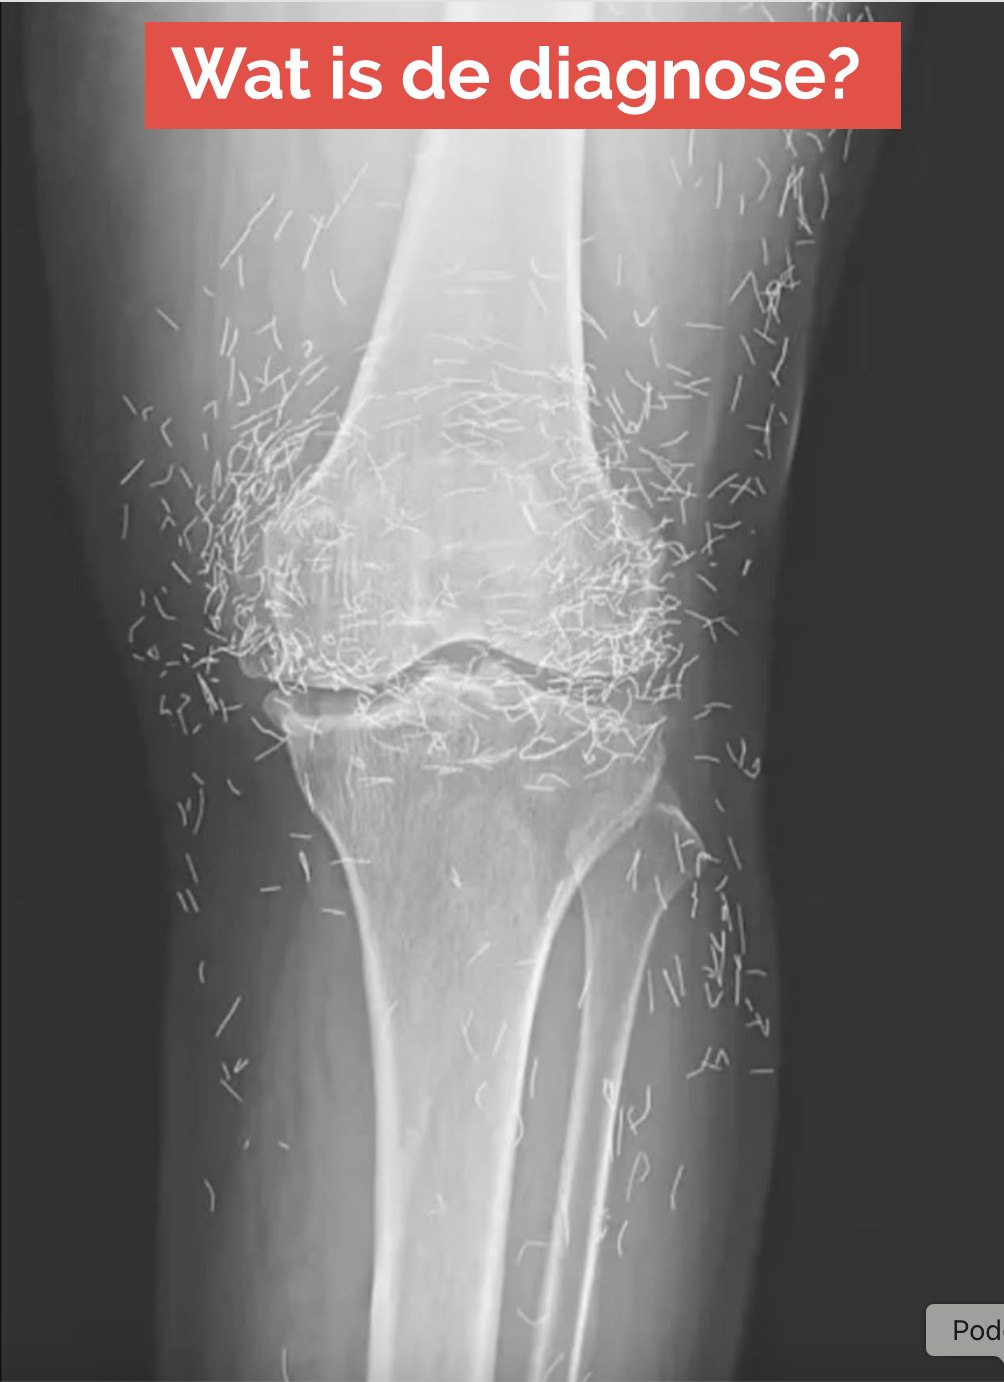

Toen een 65-jarige Zuid-Koreaanse vrouw zich meldde met kniepijn, verwachtten de artsen niet dat ze goud zouden vinden. Maar dat was precies wat ze vonden.

Daarom wendde ze zich tot acupunctuur, volgens een casus gepubliceerd in het New England Journal of Medicine.

Acupunctuur, een eeuwenoude alternatieve behandelmethode, houdt in dat naalden op specifieke punten in het lichaam worden gestoken om pijn te verlichten of ziekten te behandelen. In dit geval werden de naalden – vermoedelijk gemaakt van goud – opzettelijk in haar knieën achtergelaten voor voortdurende stimulatie.